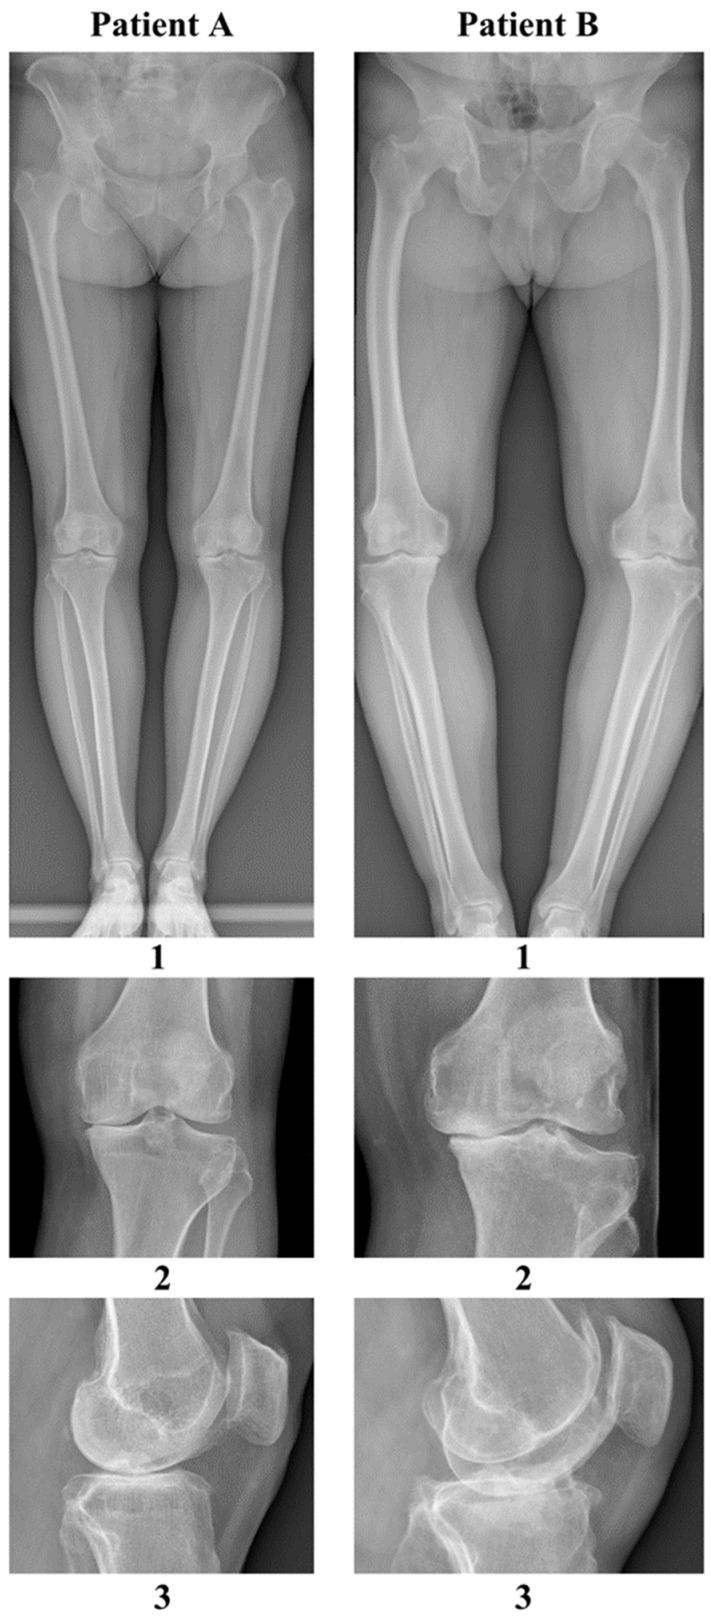

This prospective pilot study examined the association between microorganisms and knee osteoarthritis by identifying pathogens in the synovial membrane, synovial fluid, and blood samples from two patients with primary bilateral knee osteoarthritis, using metagenomic next-generation sequencing (mNGS). Intraoperatively, during routine knee arthroplasty procedures, we collected the following 12 samples from each patient: two synovial membrane samples, two synovial fluid samples, and two venous blood samples. After DNA isolation and library construction, each sample was subjected to deep whole-genome sequencing using the DNBSEQT17 platform with the read length PE150 as the default. Metagenomic sequencing data were mapped to the NCBI NT database to determine species abundance. The predominant species in all samples tested were classified under the Enterobacterales order, the most abundant being The second and third most common microorganisms detected were and autotrophic, Gram-negative bacteria sp., which is a bioaerosol component, indicating a risk of inhalation of the toxic metabolites of this latter microorganism. This article provides an initial exploration of mNGS use to study the etiopathogenetic mechanisms of knee osteoarthritis (OA). While our analysis identified bacterial DNA, particularly from , further cross-sectional studies in larger populations with and without OA are needed to determine the role of these agents in OA pathogenesis.

这项前瞻性试点研究通过使用宏基因组下一代测序(mNGS)鉴定两名原发性双侧膝关节骨关节炎患者滑膜、滑液和血液样本中的病原体,研究了微生物与膝关节骨关节炎之间的关联。术中,在常规膝关节置换手术过程中,我们从每位患者身上采集了以下12个样本:两个滑膜样本、两个滑液样本和两个静脉血样本。在进行DNA分离和文库构建后,每个样本使用DNBSEQT17平台进行深度全基因组测序,默认读长为PE150。宏基因组测序数据被映射到NCBI NT数据库以确定物种丰度。所有测试样本中的主要物种被归类在肠杆菌目下,最丰富的是。检测到的第二和第三常见微生物是和自养革兰氏阴性菌sp.,后者是一种生物气溶胶成分,表明存在吸入这种微生物有毒代谢产物的风险。本文对mNGS用于研究膝关节骨关节炎(OA)的发病机制进行了初步探索。虽然我们的分析鉴定出了细菌DNA,特别是来自的,但需要在更大规模的有和没有OA的人群中进行进一步的横断面研究,以确定这些病原体在OA发病机制中的作用。